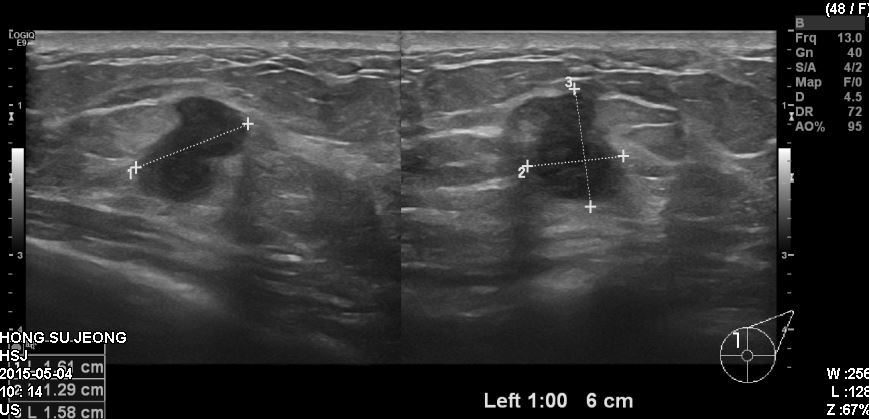

좌측 유방에 만저지는 혹으로 내원하신 40대 여성 분으로 본원에서 초음파 시행 후

좌측 1:00 방향에 6cm 떨어진 거리의 몽우리 조직검사 하였으며, 좌측 침윤성

유관암 진단 되었습니다.